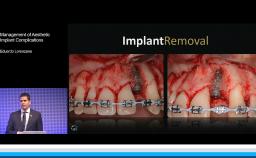

Managing Complications in Complex Restorations

This lecture discusses a wide variety of complications with prosthetic procedures. Possible causes of these complications are outlined, ranging from treatment planning to dental laboratory issues. This presentation highlights problems of poor technical decision-making and execution as well as engineering and component failures. Clinical cases with advanced and complex prosthetic failures are presented to illustrate different scenarios and situations that can occur when planning and placing implant-supported prostheses.